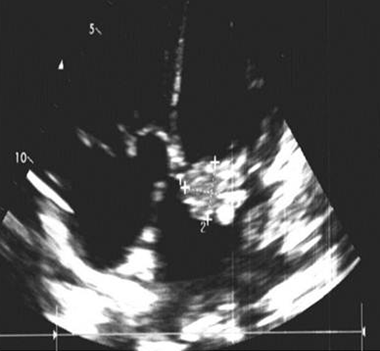

A 47-year-old male was transferred to our hospital due to fever and severe fatigue. Although he had been experiencing symptoms for several months and visited doctors near his home several times, his condition was not diagnosed and he took antimicrobial drugs for a few days. On admission, he exhibited a systolic murmur and moderate mitral regurgitation with large vegetation on echocardiographic findings (Figure 1). Streptococcus mitis was detected in his blood culture and he was diagnosed with infective endocarditis. He also exhibited Janeway lesion, petechial hemorrhage on his conjunctiva and Roth spots on his fundus (Figure 2). His clinical presentation is typical. Computed tomography scan and magnetic resonance imaging scan revealed small multiple embolization to the brain, spleen, and kidney. Cardiac surgery was too risky because he also had severe coagulopathy and his mitral regurgitation was not so severe as needed the surgery. Although intensive medical treatment was administered, his severe infection was not controlled, and it led to multi-organ failure. On day-15 of hospitalization, the patient succumbed to multi-organ failure. Autopsy revealed huge vegetation (30×15×5 mm) in the two-thirds around the mitral valve (Figure 3). Histological analysis demonstrated that the vegetation was composed of necrotic tissue and neutrophils, along with numerous Gram-positive cocci (Figure 4) that destroyed the tissue of the mitral valve and the wall of the left atrium (Figure 5). An autopsy also revealed embolization of kidney and spleen and necrotic intestines, which had caused multi-organ failure.

Figure 1: Large vegetation on the mitral valve, which swayed with moderate mitral regurgitation.